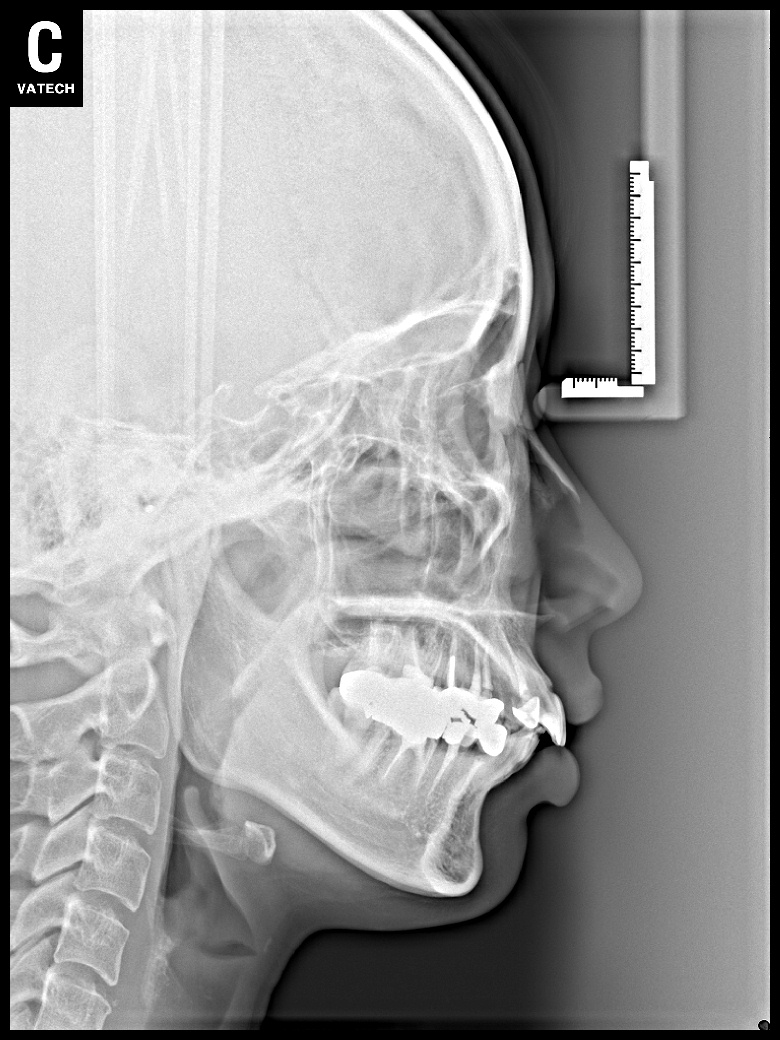

치료 전 사진입니다.